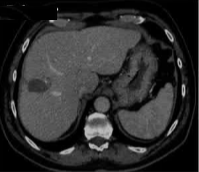

69 岁的男性患者,患有丙型肝炎相关肝硬化,其肝脏增强扫描(S8)中可见一个 22 mm 肝细胞癌结节。